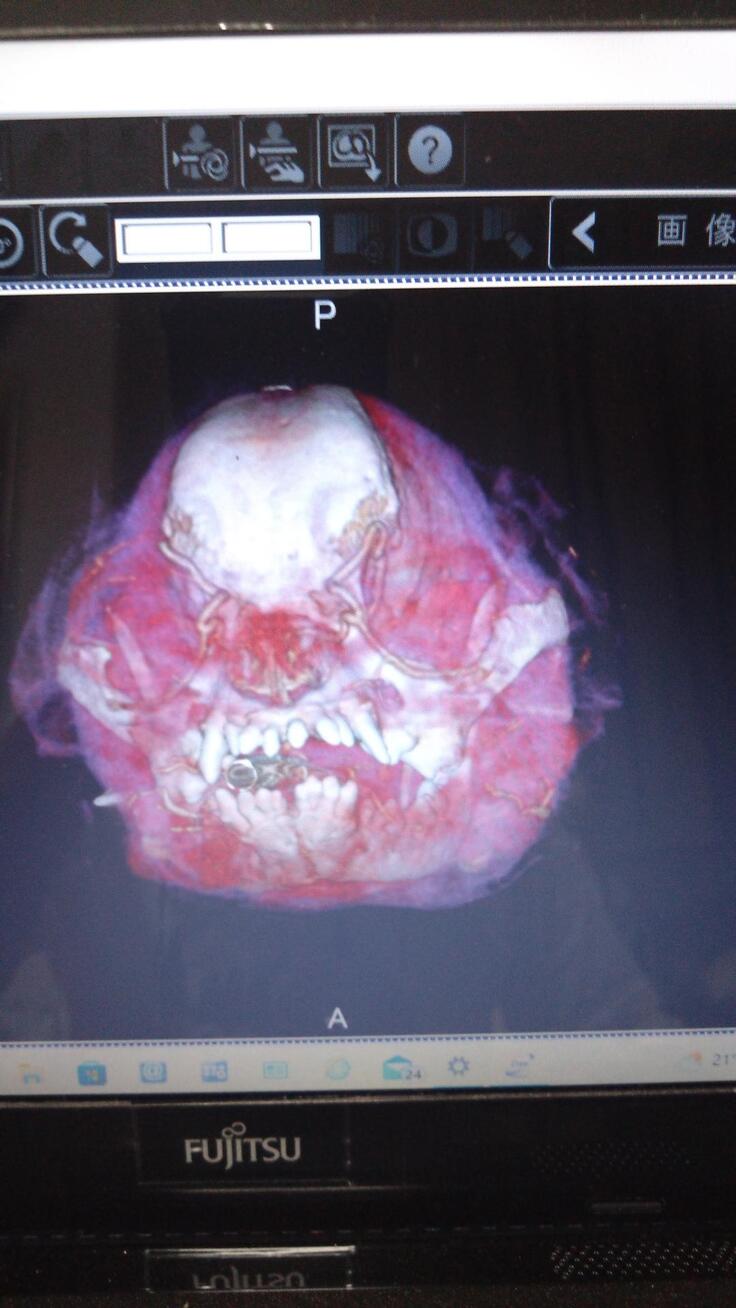

CT検査画像

パグのジョー(15歳)が悪性黒色腫(ステージ4)を発症し、進行のとても早いガンで既に肺に転移している状態で、手術はもう出来ない状態だと言われました。数年前から後両足が弱り現在は自力での歩行はできません、膀胱炎や急性肝炎など入退院を繰り返しようやく最近では体調が少し安定してきたかなと思った矢先に、御飯が左側の口からよくこぼれるようになってなにげに顎の下を触ると少し腫れているのに気づき、すぐに病院で診察してもらいましたが、詳しい検査をしないと分からないとのことで、腫瘍専門がある病院を紹介してもらい、造影剤を使用したCT検査、組織検査の結果、口腔悪性黒色と診断され腫瘍の大きさや肺に迄転移していることから手術は出来ないとのことで放射線治療しか有効な治療はないと言われました。ガンの進行が早く、何も治療をしないと口腔が壊死していく可能性があると説明され、根治は困難ですが、せめて最後迄御飯を食べてもらいたいと思い、放射線治療をしてあげたいと思いました。しかし、高額の検査費と治療費の為、放射線治療するのはかなり困難と半ば諦めていた時に、この活動を知り、せめてもう少しでもジョーとの時間を過ごせるように、皆様のご支援よろしくお願いいたします。

CT検査(造影剤)